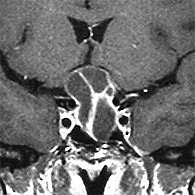

Μαγνητική τομογραφία πριν το χειρουργείο